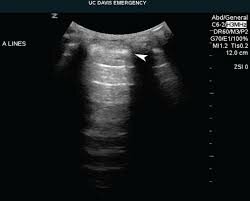

• Lung and General Sonography

Lung and General Sonography

Professor Daniel Lichtenstein began incorporating lung and general sonography in intensive care units. Which is basically a chest ultrasound is a noninvasive diagnostic exam that produces images, which is used to assess the organs and structures within the chest, such as the lungs.